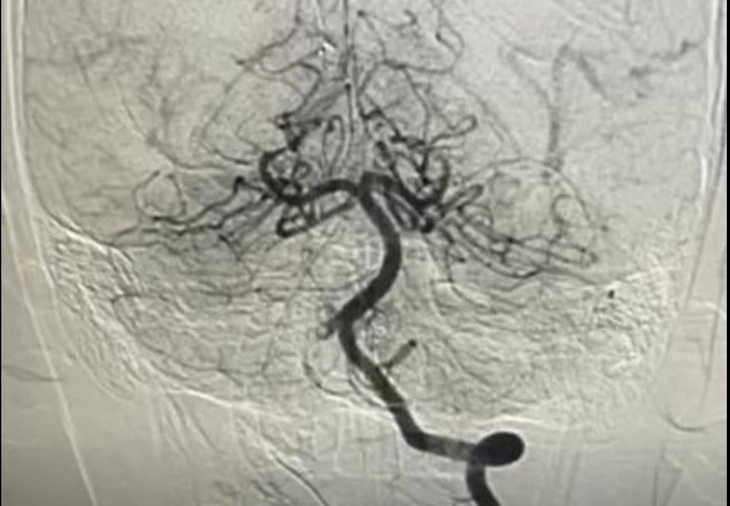

Ảnh chụp mạch máu xóa nền DSA của bệnh nhi 10 tuổi bị nhồi máu não cấp - Ảnh: Bệnh viện cung cấp